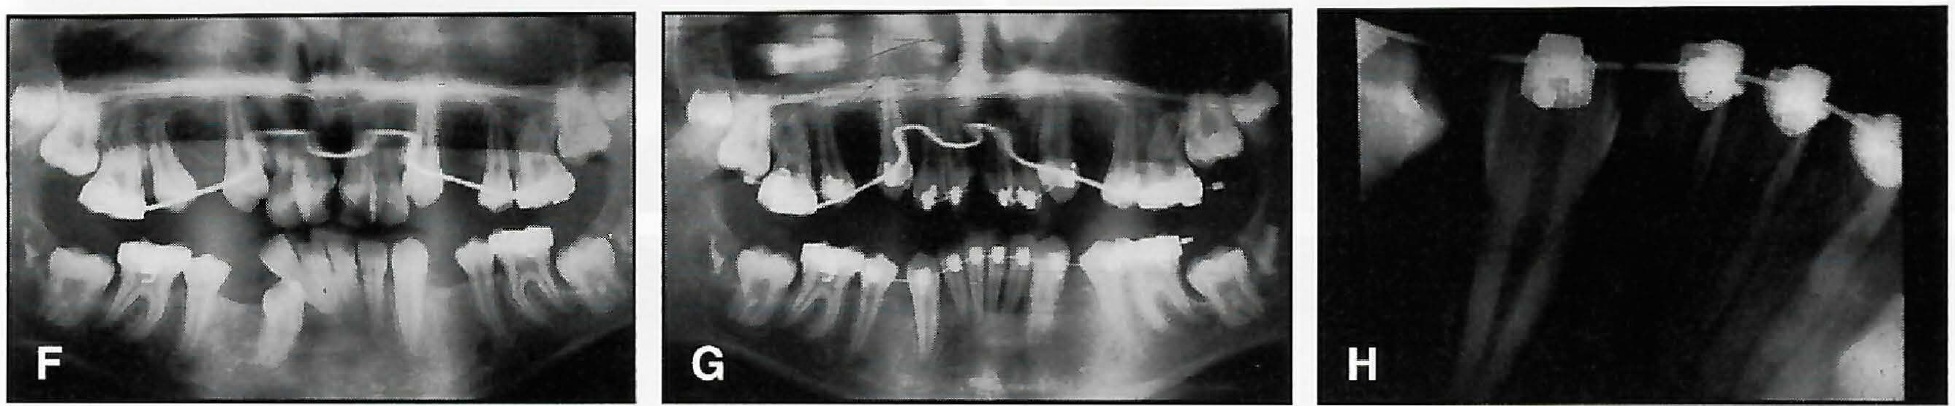

The resilience of Supercable makes it impossible to place distal end bends. Flaming the wire ends only results in fraying. Therefore, specially designed Supercable distal end stops must be added to secure the wire distal to the terminal brackets (Fig. 5). A SPEED Supercable Stop Plier or a blunt distal end cutter can be used to simultaneously place and crimp the stop. Alternatively, light-cured composite material can be placed over the protruding archwire ends, replacing the crimpable stops, or the composite can be cured over the stops to enhance mechanical retention (Fig. 6).

Fig. 5 Supercable stop crimped and seated snugly against mini-molar tube.

Fig. 6 Light-cured composite applied to cover distal end of Supercable.